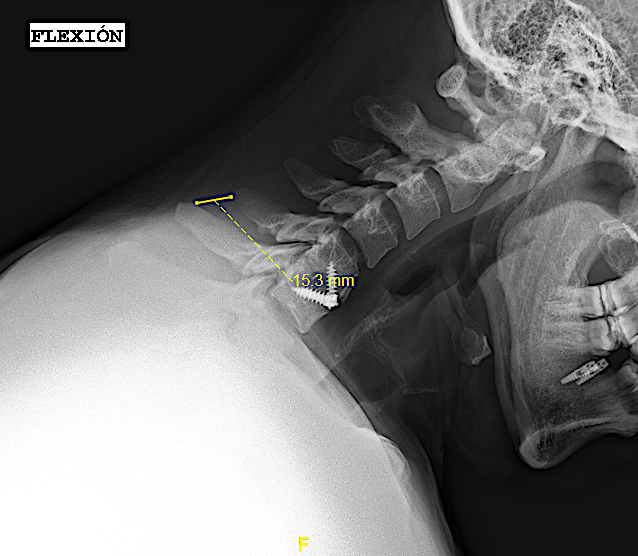

- «fijación intersomática» cuando en las RX funcionales no se aprecia movimiento sin ver «puentes óseos». Puede valer para este apartado el criterio de hallar una diferencia de <1mm entre la distancia de las respectivas apófisis espinosas en flexo/extensión o, si las espinosas no se visualizan o no están presentes, una angulación de platillos <3º también en las RX dinámicas. A estos pacientes les realizo un seguimiento anual con Rx (hasta visualizar puentes óseos o durante 3 años).

Mismo paciente de la imagen anterior; ahora en flexión. Obsérvese que, pese a estar fusionado es difícil obtener la misma medida al medir la distancia interespinosa